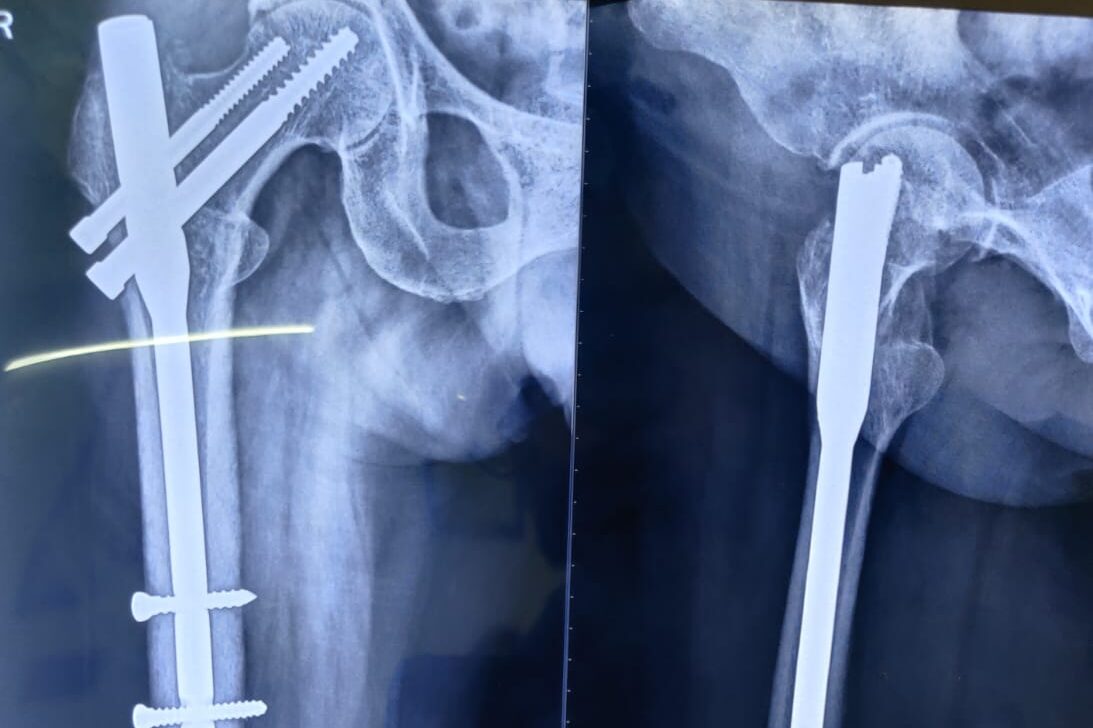

Complex Trauma & Fracture Management

- Polytrauma & Multiple Fracture Care

- Pelvic & Acetabular Fracture Surgery

- Open & Complex Fracture Fixation

- Non-union & Malunion Correction

- Emergency Trauma Care & Stabilization